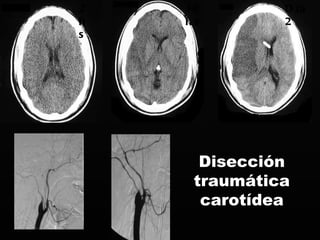

Disección traumática carotídea 2 hs 10hs Día2

Fracturas de labase de cráneo Anterior Rinorragia y/o rinorraquia Pneumo encéfalo Nivel líquido en s.p.n. Equimosis periorbiraria Infección Déficit Neurológico Trauma vascular Oclusión Fístula CC